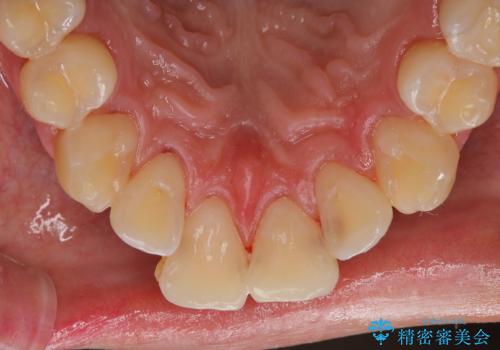

セラミックを付ける前にエアフローで綺麗ににクリーニング

- セラミックの詰め物を付ける前に、全体のクリーニングを希望とのことでした。

染め出しをし、歯磨き指導とクリーニング(エアフロー60分コース)を行いました。